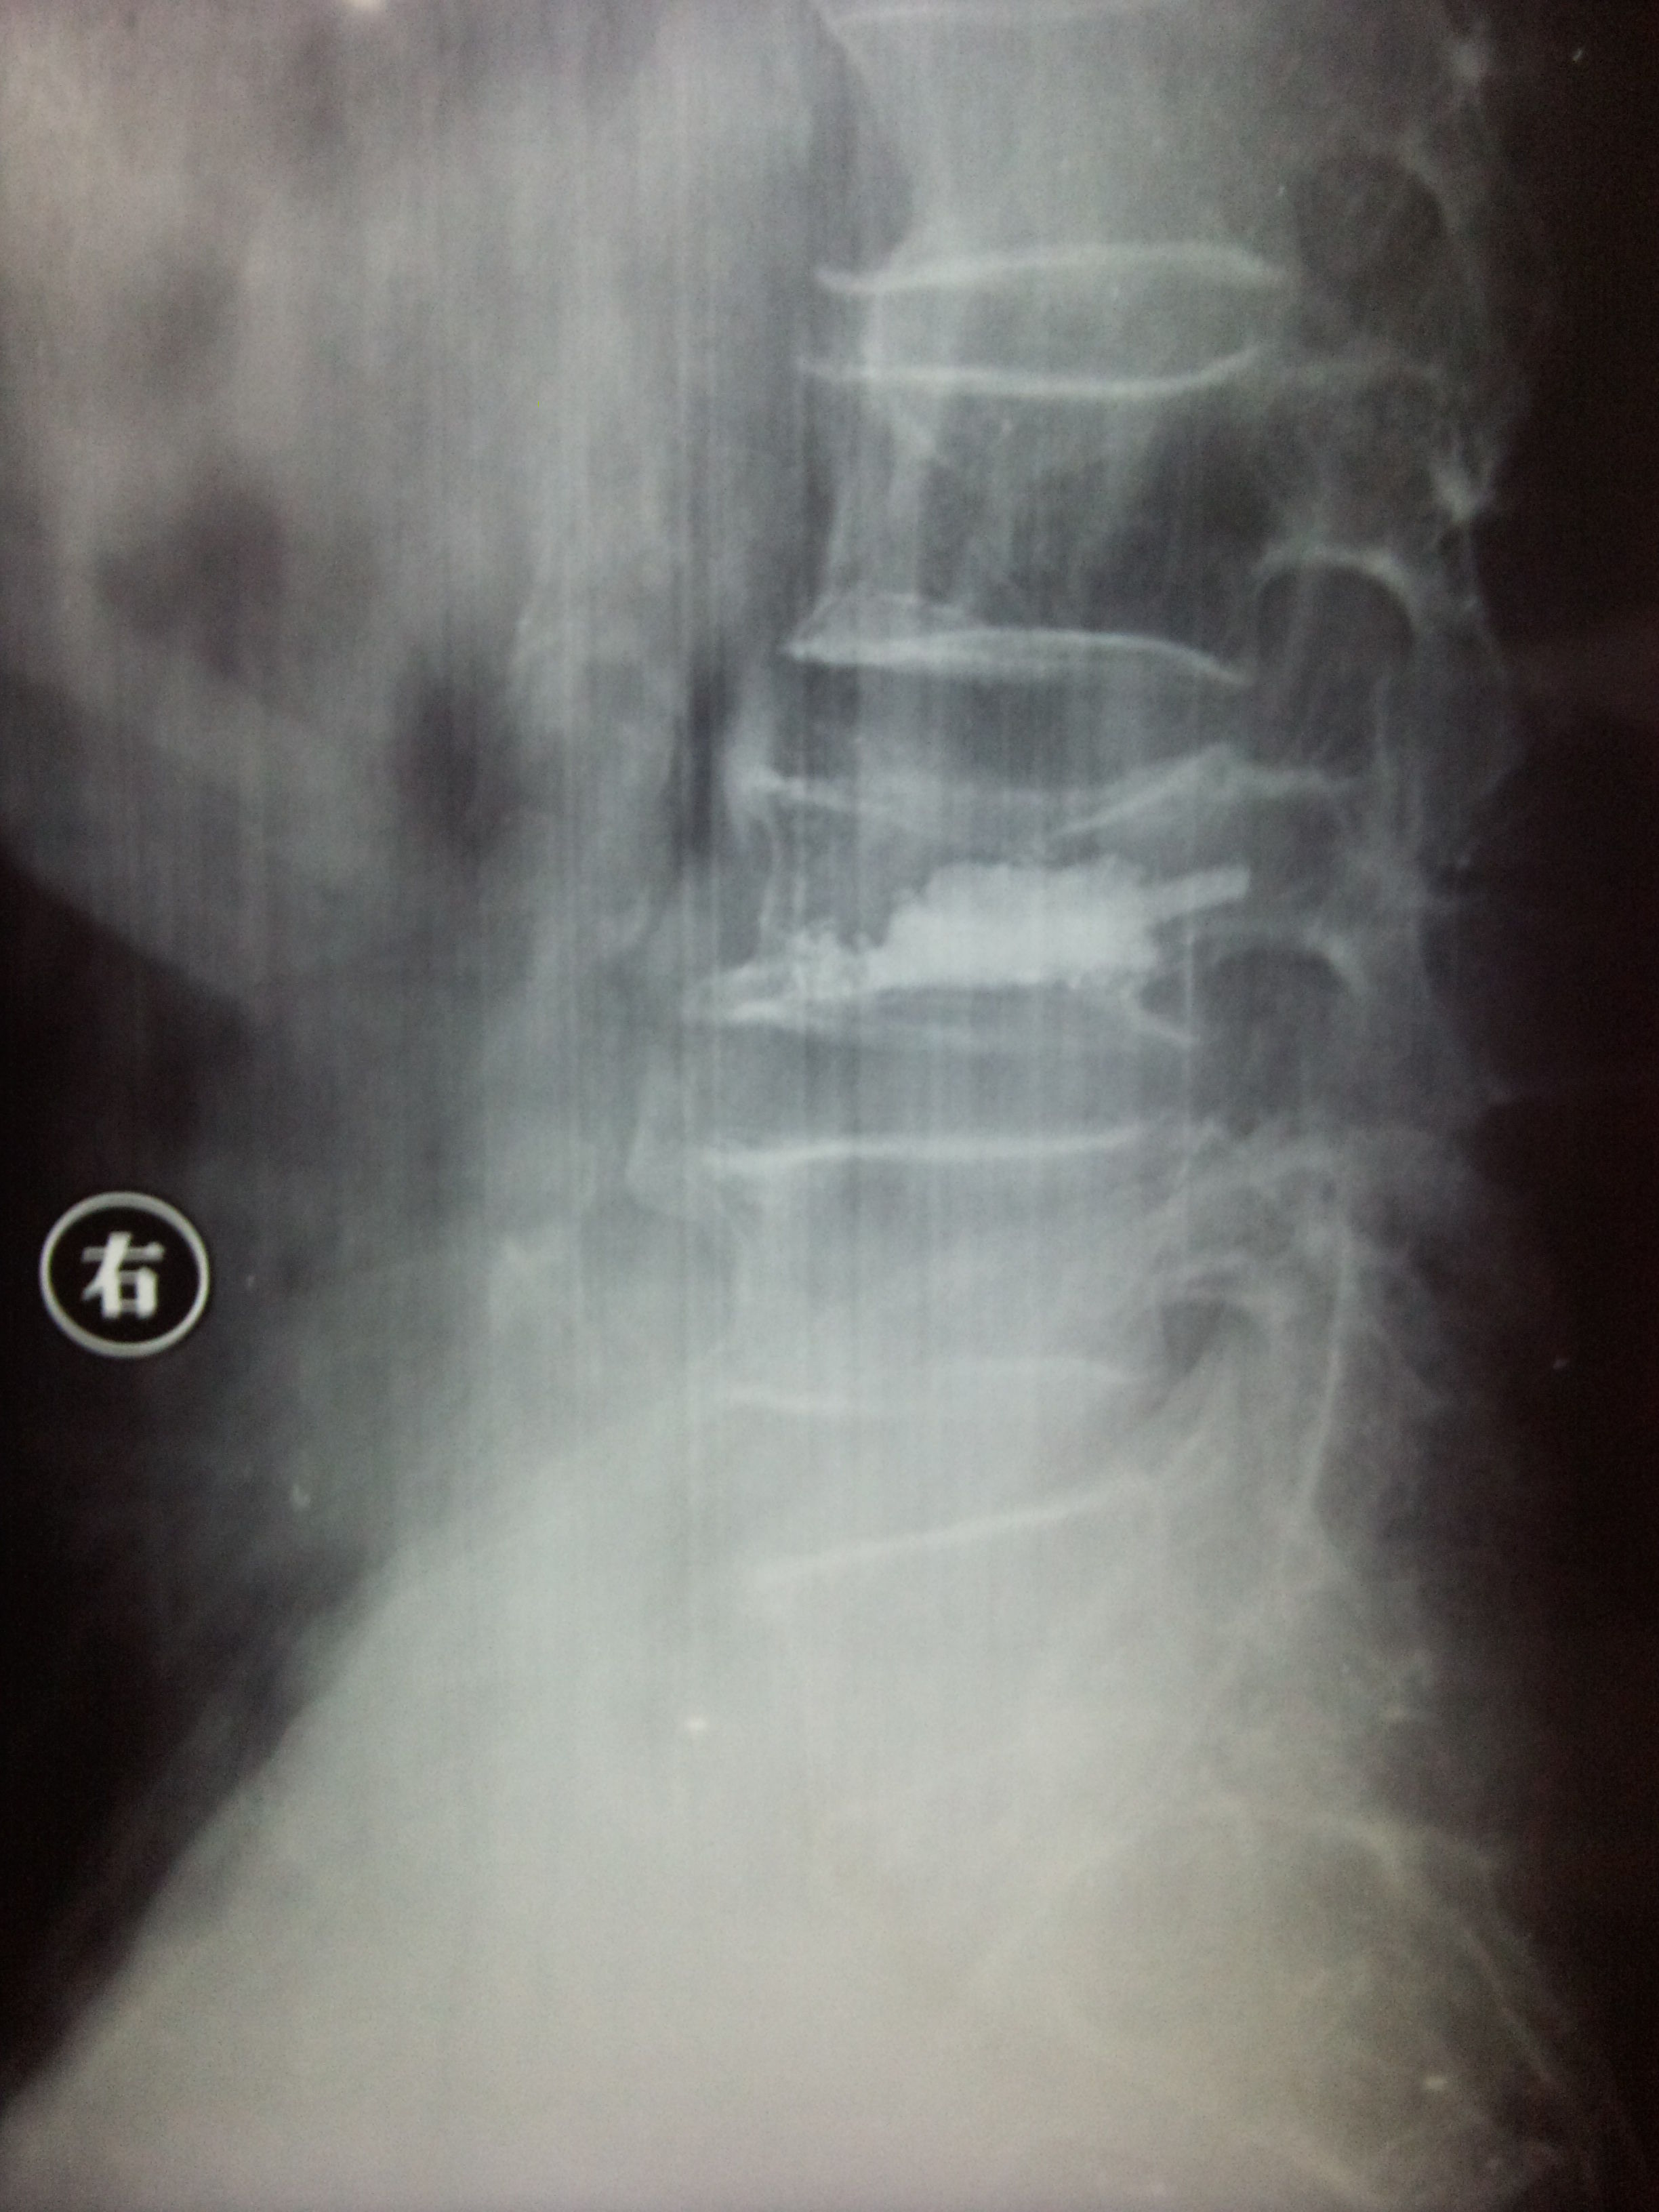

入院后经积极术前准备,于2010年12月27日下午在局麻下行经皮穿刺球囊扩张椎体成形术。下图为手术创口及术后X光片。两个切口各缝合一针。